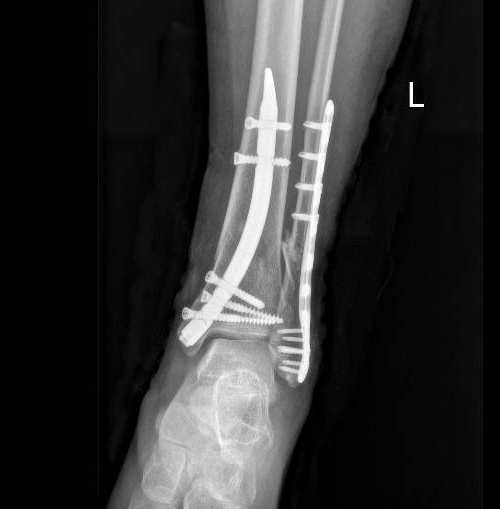

患者入院后,我们迅速完善了相关检查,结果显示其为AO/OTA A3型骨折,这一类型骨折恰好是进行胫骨逆行髓内钉手术的绝对适应症。在周钢主任的精心指导下,并且在与患者及其家属充分沟通、获得知情同意后,我们为患者实施了左胫骨远端骨折逆行髓内钉内固定术,同时进行了左外踝骨折的切开复位内固定手术。手术过程顺利,取得了预期的成功。

DTN术后复查DR